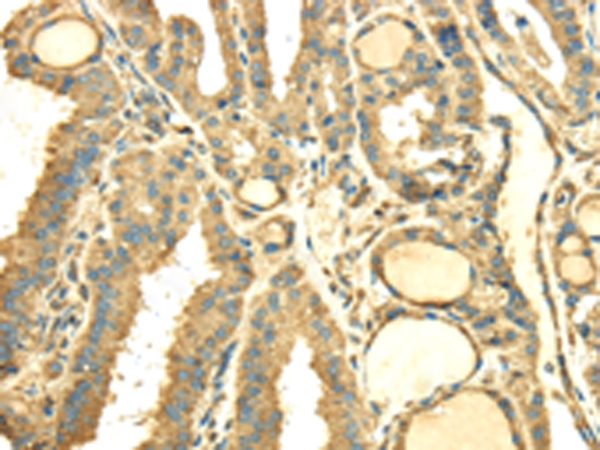

分类: 科研抗体货号: P08745别名: Cab45; SDF-4应用: IHC反应种属: Human, Mouse, Rat